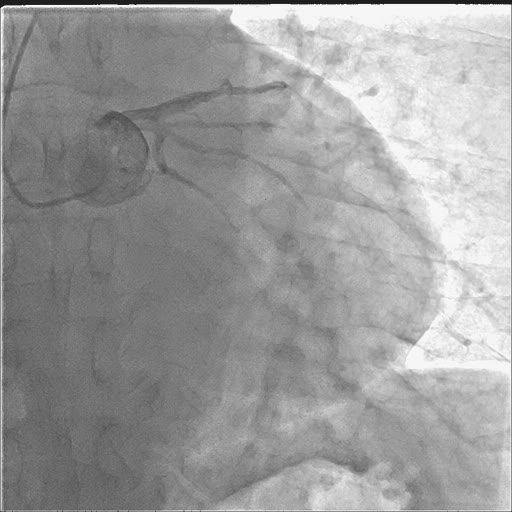

造影如下:

在透视进导丝的过程中就发现了问题--心脏游离缘出现“透亮带”!!!

抓紧时间完成造影: